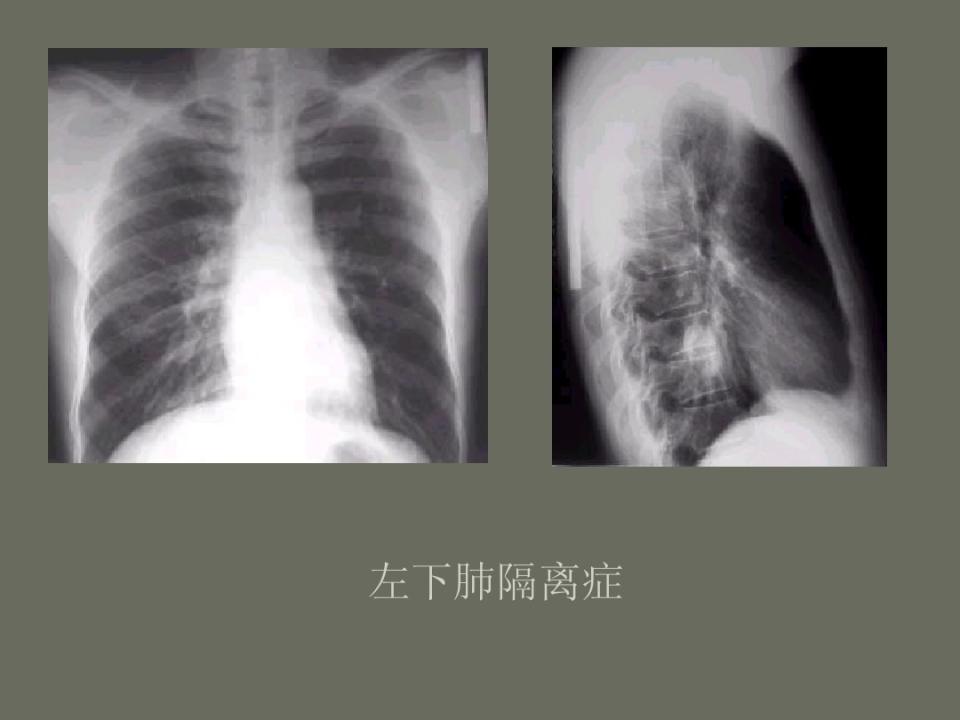

肺部先天性疾病的影像诊断